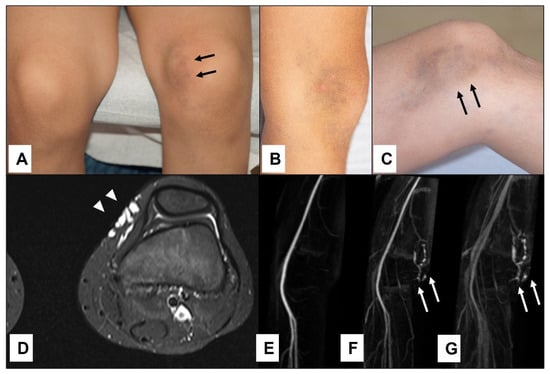

Figure 1.

A 3-year-old boy with a pulsatile lesion under the malleolus lateralis of the left foot (D)—(black arrows). MRI showed a localized arterio-venous malformation in the subcutaneous tissue (A,B) with an AV shunt in the MR-angiography (C)—(arrowhead) depicted by the early visualization of the vein (C)—(yellow arrows). Complete surgical excision was performed (E) with ligation of the feeding artery (F)—(yellow arrows) and the draining veins (F)—(arrowhead).

Figure 2.

An 11-year-old boy presented with bluish swelling medially on the left knee (A): white (arrowheads). The lesion was compressible and would drain and flatten with the elevation of the leg indicating clinically the venous malformation (B,C)—(white arrowheads). MRI showed the exact location and extension of tubular-cystic venous malformation (D)—(white arrowheads), which filled with contrast material in the venous phase of the MR angiography (E–G)—(white arrows), confirming the clinical diagnosis. The patient was referred to sclerotherapy.